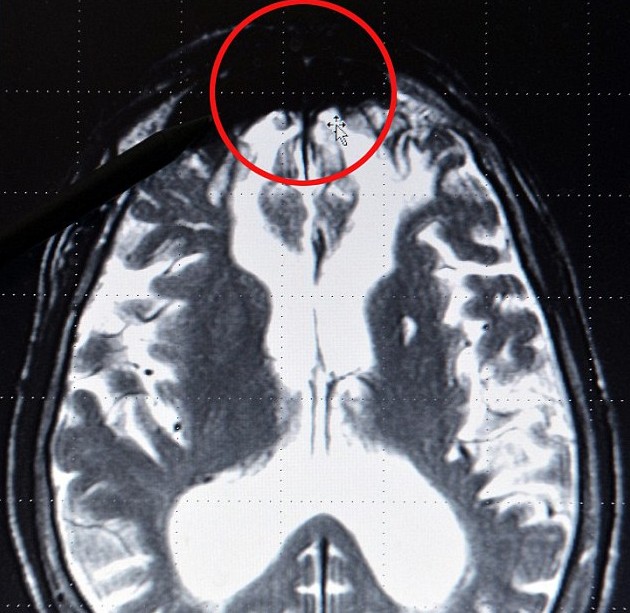

“邪惡片區(qū)”位于大腦前端。

通過觀察年輕人的大腦X光片,羅特博士推測出前額處大腦機(jī)能潛在失調(diào)的人,將有66%的可能性實(shí)施暴力犯罪。根據(jù)他的理論,沒有兩個(gè)暴力罪犯是相同的,但他們主要可以分為三大類:第一種是心理健康但受到環(huán)境影響而從事打、偷、搶等犯罪活動(dòng);第二種是精神受過刺激的人,他們對周圍世界懷有敵意和脅迫感;第三種是純粹的精神變態(tài),就像希特勒那樣的極端分子。